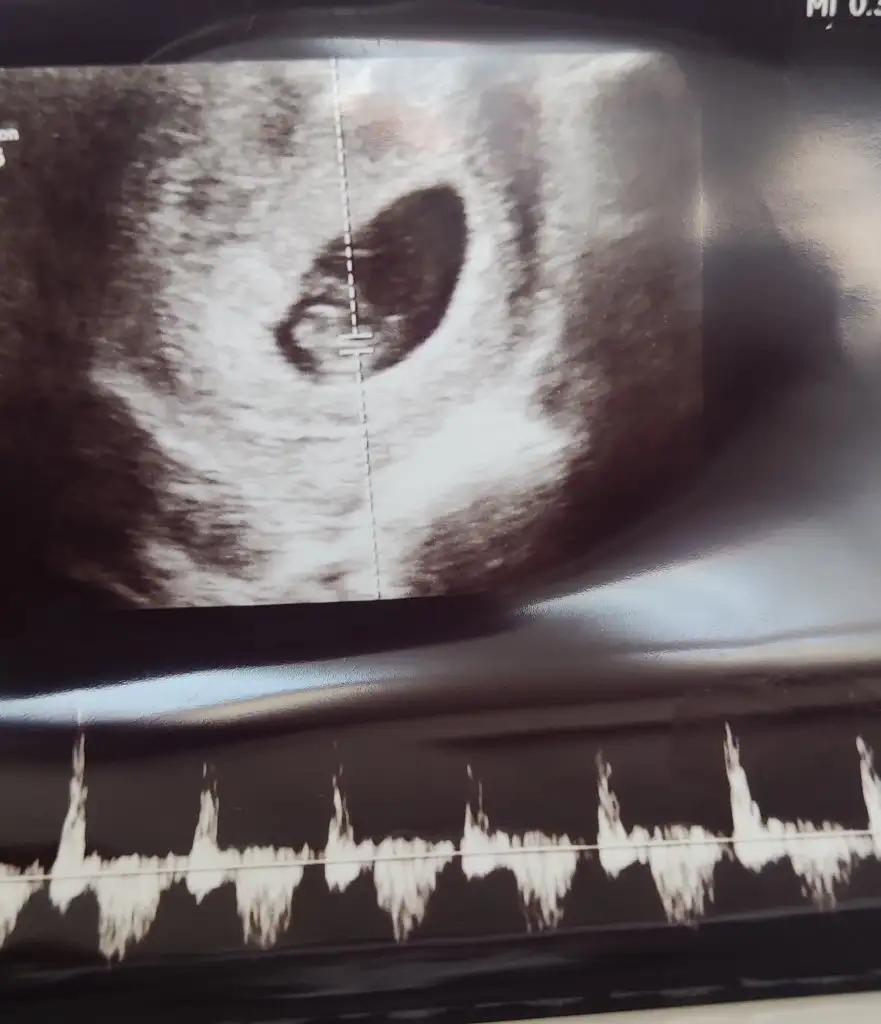

Merhaba benim içinde bir tahminde bulunabilir misiniz ?

Merhaba karından ultrason 8 haftalık banada tahminde bulunur musunuz ?